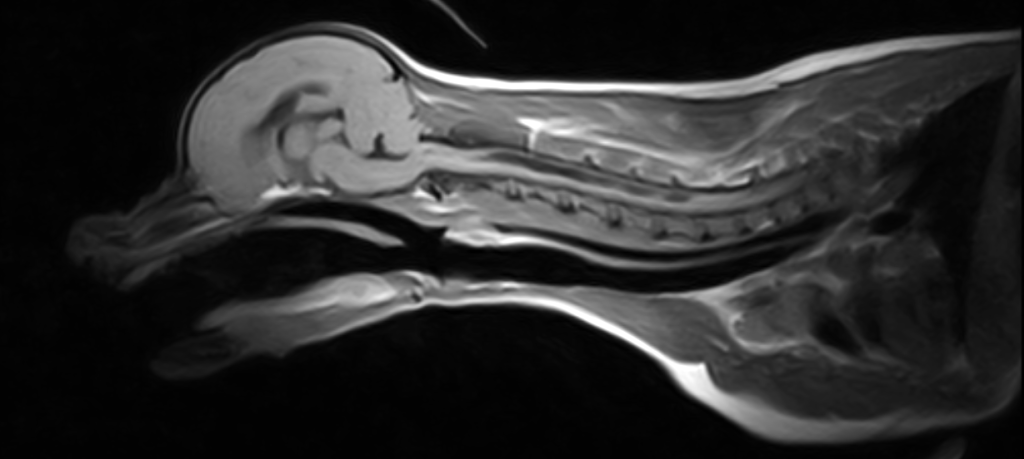

Chiari-epämuodostuma ja syringomyelia

Chiari –tyyppinen epämuodostuma (CM) tarkoittaa aivojen takakuopan suhteellista ahtautta (aivojen takakuopan tilavuus on siis suhteellisesti liian pieni sen sisältämän aivokudoksen määrään nähden), minkä seurauksena pikkuaivot ja usein myös aivorunko tyräytyvät taaksepäin kallon isoon aukkoon (foramen magnumiin) tai sen läpi.

Syringomyelia (SM) tarkoittaa nesteentäyteisten onteloiden muodostumista selkäytimeen aivoselkäydinnesteen epänormaalin liikkumisen seurauksena. Tärkein syringomyelialle altistava tekijä on Chiari –tyyppinen epämuodostuma.

Yleisin syringomyelian aiheuttaja on pikkuaivojen työntyminen selkäydinalueelle kallonpohjan ison aukon kautta (Chiari-epämuodostuma).